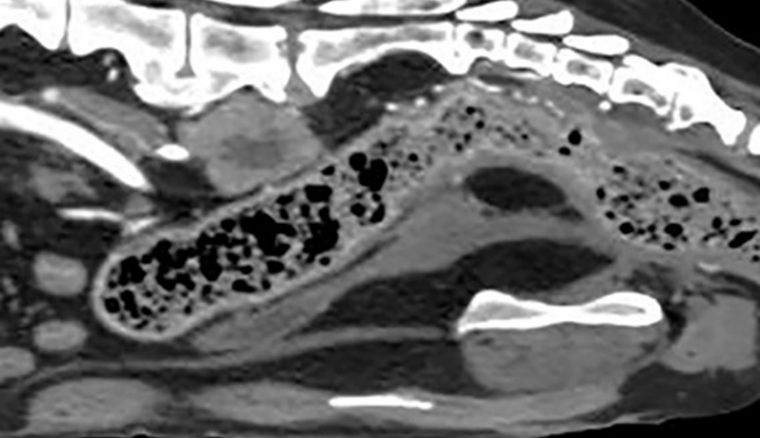

Mercredi 5 Septembre 2018 Animaux de compagnieReconstruction sagittale d'un scanner abdominal.

© Service d'imagerie ENVA